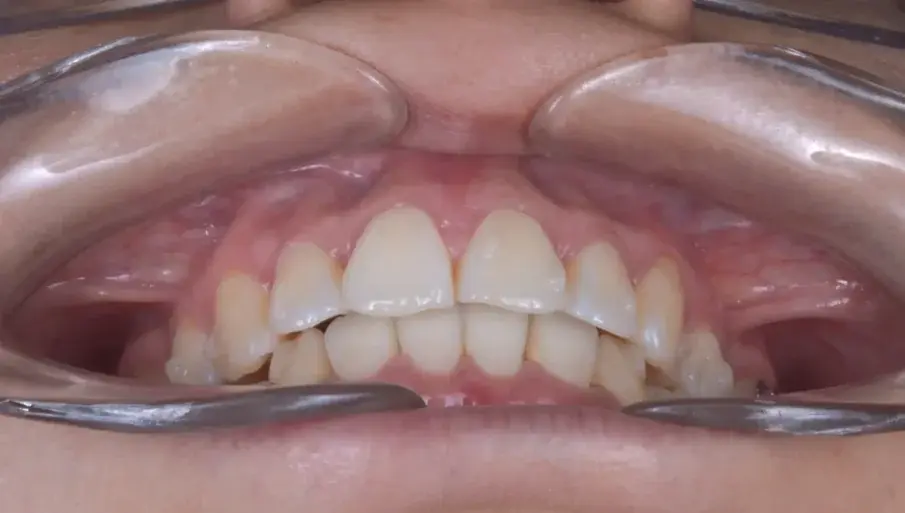

Фиг. 2а: Първоначални интраорални изображения.

Фиг. 2b: Първоначални интраорални изображения.

Фиг. 2c: Първоначални интраорални изображения.

35-годишна пациентка постъпва със струпване на зъби, болки в мускулите и ставите и главоболие след събуждане. При прегледа се установява I скелетен клас със струпване и бимаксиларна протрузия. Изследването на лицето показа конвексен профил с изпъкнали устни и квадратна форма на лицето, която се засилва при усмивка (фиг. 1-4). Тя съобщава за бруксизъм и се наблюдава двустранна хипертрофия на масетерите, но няма изменения в темпоромандибуларните стави.